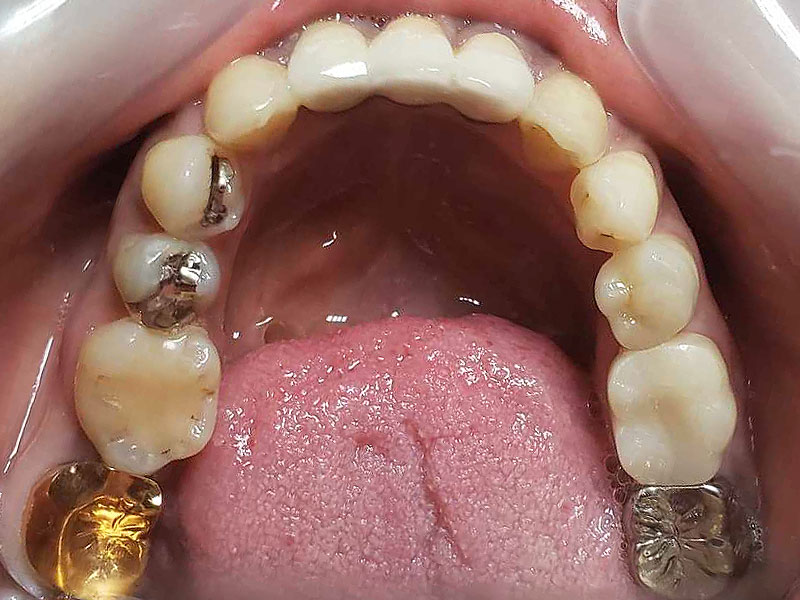

術前

- 初診:2006年。2010年―矯正治療を含めた一口腔単位の治療開始、治療当時、30代女性、喫煙者

- 主訴:虫歯治療、歯周病治療、できれば歯並びも治したい。

- 矯正診断:3級骨格性の反対咬合

- 治療方針:以前に治療した歯の再治療(虫歯治療、歯内療法、歯周処置)、右下前歯1本抜歯、矯正用インプラントを用いたワイヤー矯正、修復処置(被せ物)、保定(上ワイヤー、下マウスピース)、歯茎のピーリング(漂白)、4か月メンテナンス